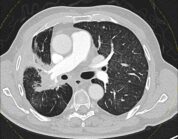

Lungenkrebs: Höhere Strahlendosis ist sicher und vielversprechend

Eine Studie von Forschenden der Karl Landsteiner Privatuniversität für Gesundheitswissenschaften in Krems (Österreich) zeigt, dass eine intensivere Strahlentherapie bei Lungenkrebs das Risiko für entzündliche Reaktionen nicht erhöht, aber möglicherweise die Überlebenschancen verbessert.